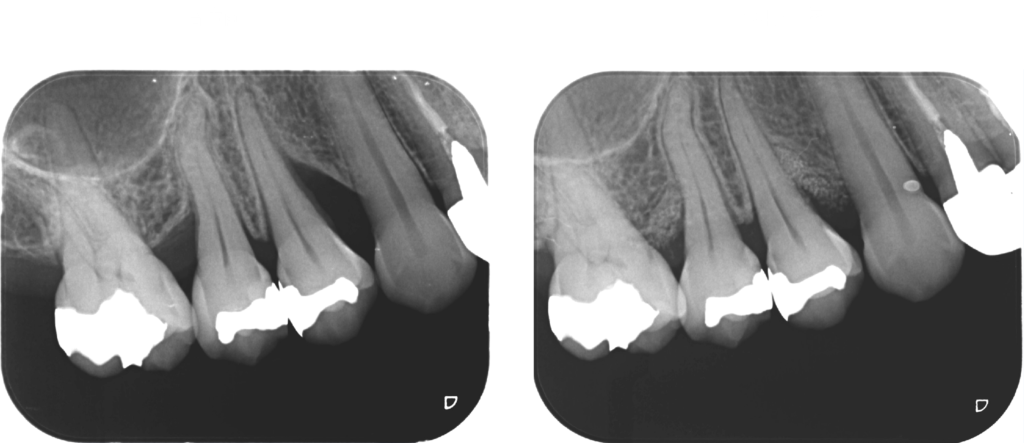

こちらの症例は51歳女性です。

矢印の部分の骨(歯槽骨)が溶けています。

歯肉を開いて歯肉の中の歯根面に付着している歯石や骨(歯槽骨)が溶けている中の不良肉芽(正常でないない軟組織)を徹底的に除去し、

再生材料と人工骨と填入し、縫合しました。

術前と術後1年半の比較です。

骨様組織で骨(歯槽骨)が溶けていた部分が満たされていることが確認できます。

歯肉退縮も最小限で良好な歯周組織を維持しています。